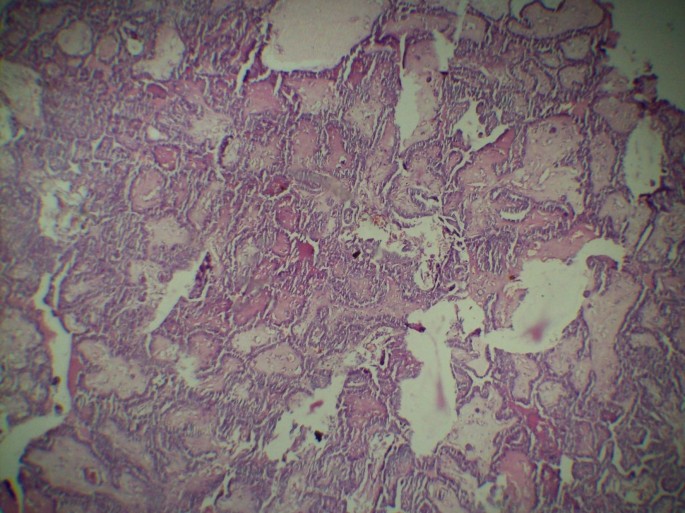

Фотографии опухоли медуллярной аденокарциномы

Раздел: Снимки-откровения